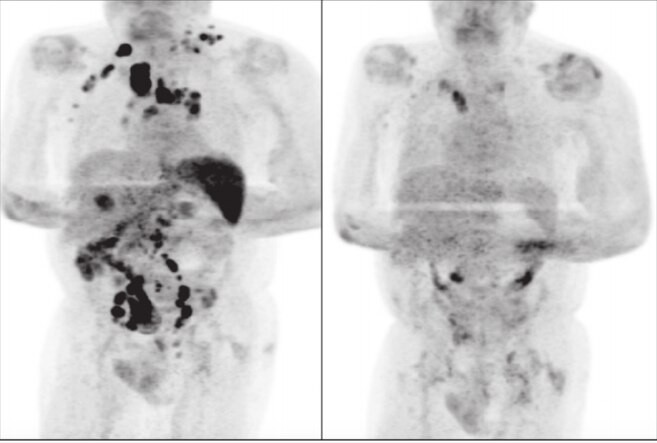

Cuatro meses más tarde, durante una exploración, los médicos advirtieron que la inflamación de sus ganglios al tacto había remitido. Le hicieron una tomogarafía y advirtieron una remisión generalizada del linfoma.